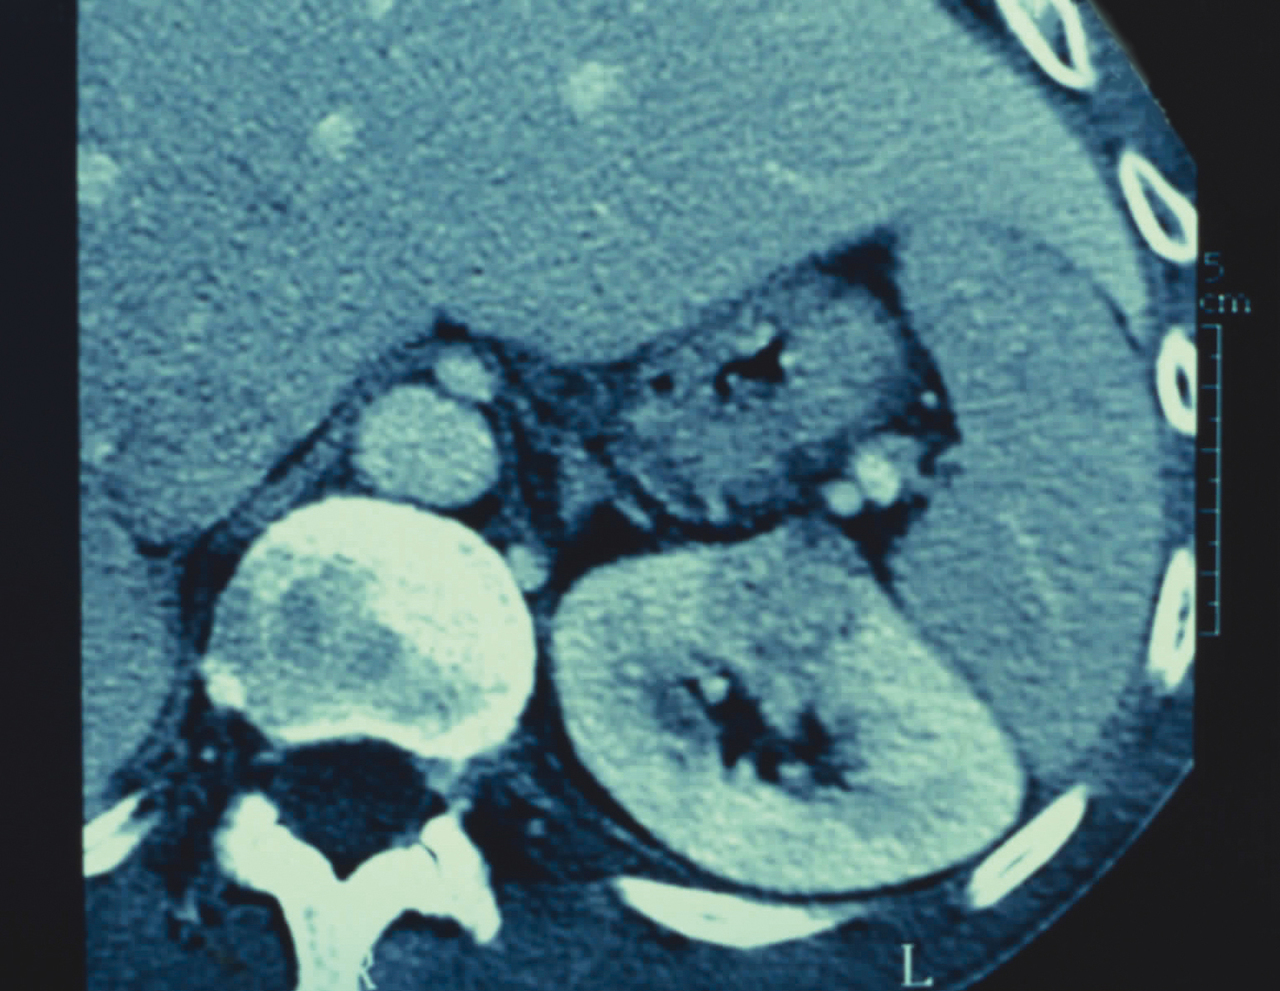

Quel est votre diagnostic ? Cancer du rein Il s'agit d'un cancer du rein.Pour en savoir plus : -Desgrandchamps F, et al. Dossier Traitement du cancer du rein. Rev Prat 2018;68(1):41-55. - Flamand V, Lamandé N. Tumeurs du rein. Rev Prat 2017;67: spécial web. Abcès du rein Kyste rénal Angiomyolipome Hydatidose OK Valider mes réponses